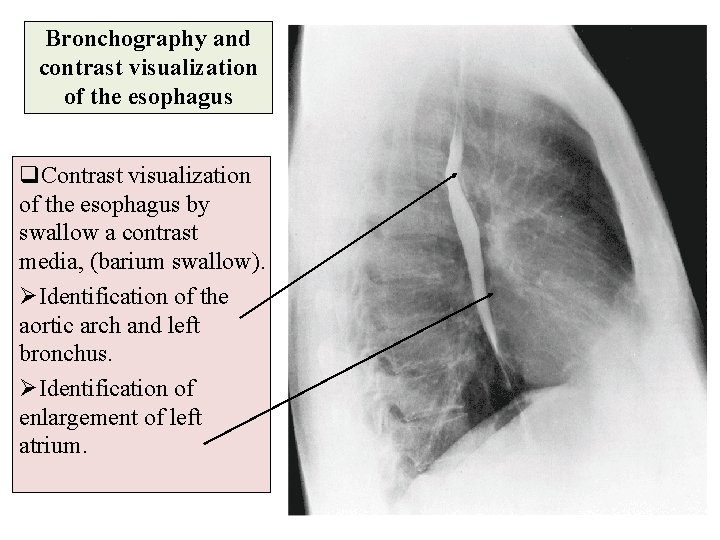

Bronchography and contrast visualization of the esophagus q. Contrast visualization of the esophagus by swallow a contrast media, (barium swallow). ØIdentification of the aortic arch and left bronchus. ØIdentification of enlargement of left atrium.